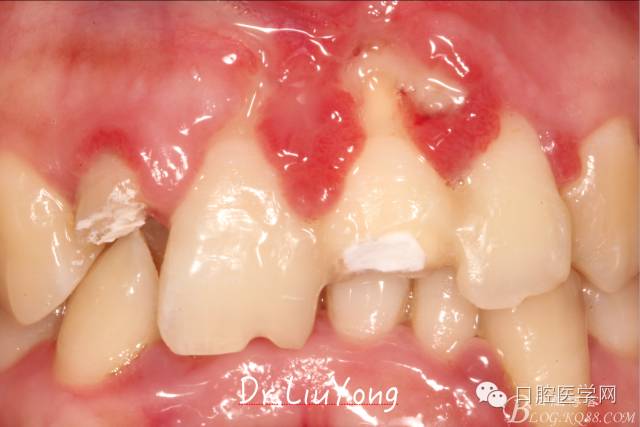

松動牙固定一月后拆除,A1-B2無明顯動度,但牙齦紅腫加重,給予全口齦上下潔治刮治術(shù),上藥,醫(yī)囑加強口腔衛(wèi)生,氯己定漱口液含漱。

術(shù)后兩周復(fù)查,牙齦紅腫明顯好轉(zhuǎn),探診不出血,但是此時A1唇側(cè)牙齦角形退縮1.5mm,B1唇側(cè)牙齦退縮3.5mm,B1遠中牙齦乳頭萎縮明顯,B2近中牙齦萎縮約1mm,且A1B1B2牙齦退縮處角化牙齦幾乎缺失,同時上唇系帶直接牽拉于B1齦緣?;颊邽楦咝€女性,露齦笑,由于存在前牙區(qū)牙齦的高度嚴(yán)重不對稱及前牙牙冠過長的問題,因此嘗試通過膜齦手術(shù)改善患牙牙齦退縮。通過術(shù)前分析,A1唇側(cè)牙齦退縮屬于Miller分類第一類, B1唇側(cè)牙齦退縮屬于Miller分類第3類(B1遠中牙齦乳頭為2類,Nordland and Tarnow分類法),B2唇側(cè)牙齦退縮屬于Miller分類第3類,由于擬采用冠向復(fù)位瓣的方式治療牙齦退縮,因此需要先行上唇系帶修整術(shù),解除上唇系帶帶來的過大牽引力。

潔治刮治后2周,如上圖